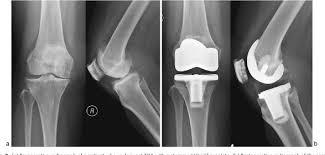

Q

Describe deformity seen. When performing TKR to either knees, how would you perform soft tissue balancing for correction of this deformity?

There is varus deformity, a coronal plane deformity.

There is concave (ST tight) and convex side (ST loose/strecthed).

Always start with tight side/ concave side first, which is medial side in this deformity.

Sequence of medial compartment release

1. Osteophytes

2. Deep MCL & Medial knee capsule

3. Posterior Medial Corner - capsule, semimembranosus.

4. Superficial MCL

i) Posterior oblique portion - if medial extension tightness

ii) Anterior portion - if medial flexion tightness

A

On this xray, there is valgus deformity in the coronal plane.

There is concave (ST tight) and convex side (ST loose/stretched).

Always start ST release at the tight side/ concave side first, which is lateral side in this deformity.

With the knee in extension

Sequence of lateral compartment release

2. Lateral capsule

3. Iliotibial band - tight in extension

then flex the knee

4. Popliteus - tight in flexion

5. Lateral collateral ligament - always last